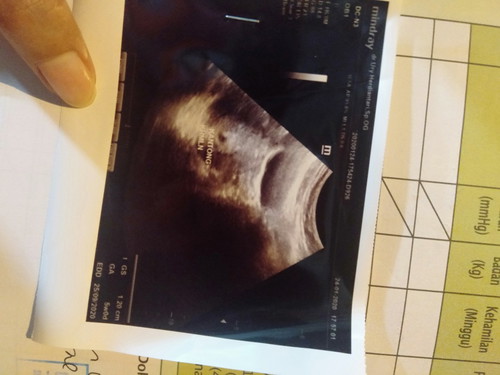

Ada yg 5w baru kelihatan kantong? 1.20cm kantong kehamilan saya..

Normal kok 5week bru keliatan kantungnya aja, saya juga gitu Tar kalo udh 7week baru udah keliatan janinnya tpi masih kecil banget bun

Normal bun, tiap ibu hamil beda beda.. saya pas periksa pertama 4w baru kelihatan kantong. 6w usg lagi sudah ada janin dan detak jantung nya

Sy pas 5w malah kantungnya baru 0,39 cm.. seminggu yg lalu terakhir usg Alhamdulillah panjang janinnya normal sesuai HPHT